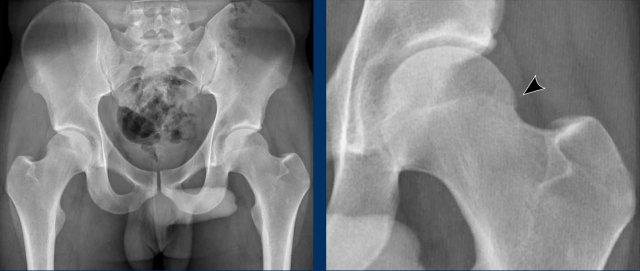

Hình ảnh

Vận động viên thể dục dụng cụ 20 tuổi với các triệu chứng ở hông.

Trên phim chụp AP, vùng đầu-cổ xương đùi trông bình thường.

Trên phim chụp tư thế Dunn, có hình thái Cam ở cả hai bên (mũi tên).